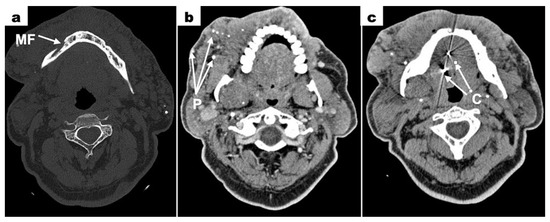

Cone-beam computed tomography (CBCT—cone-beam computed tomography) scans of the mandible, which were provided by the patient, revealed bone resorption around tooth 31. The lateral surfaces of the apices of teeth 41 and 32 were adjacent to the periapical lesion of tooth 31 (Figure 3a). Tooth 46 was treated endodontically for a deficiency of filling material in the apical region of the roots (Figure 3b). Tooth 47 showed a carious lesion. Tooth 36 exhibited extensive periapical changes (Figure 3c). Tooth 38 was partially retained in the horizontal, mesial-angular position with no eruption potential. No inflammatory cysts were found around the crown of the retained tooth. There were no signs of resorption of tooth 37 (Figure 4a). However, the distal root surface of tooth 37 was exposed due to the adjacent position of tooth 38, enabling plaque retention. This might be a potential source of inflammation (Figure 4b). In the event of peri-coronal inflammation, tooth 38 will be eligible for an extraction in the hospital setting. CBCT scans revealed areas of bone thinning in the chin region, potentially due to irradiation treatment when the patient was at the developmental age (Figure 4c).

Figure 4. Mandibular CBCT examination scans before initiation of treatment; (a) an axial plane scan—tooth 38 retained in the horizontal, mesial-angular position; (b) a sagittal plane scan—tooth 37 distally exposed due to the adjacent position of tooth 38, no signs of root resorption; (c) a frontal plane scan—between tooth 37 and 38, visible potential plaque retention; (d) anteroposterior projection—bone thinning in the chin region.